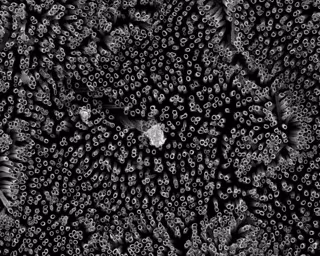

Nanotubos de titanio repelente a la sangre

KOTA LAB/COLORADO STATE UNIVERSITY

Los investigadores analizaron las variaciones de las superficies de titanio, incluyendo diferentes texturas y químicas, y compararon el grado de adhesión y activación plaquetaria. Los nanotubos fluorados ofrecen la mejor protección contra la coagulación y por ello también planean llevar a cabo estudios para ver su fiabilidad.